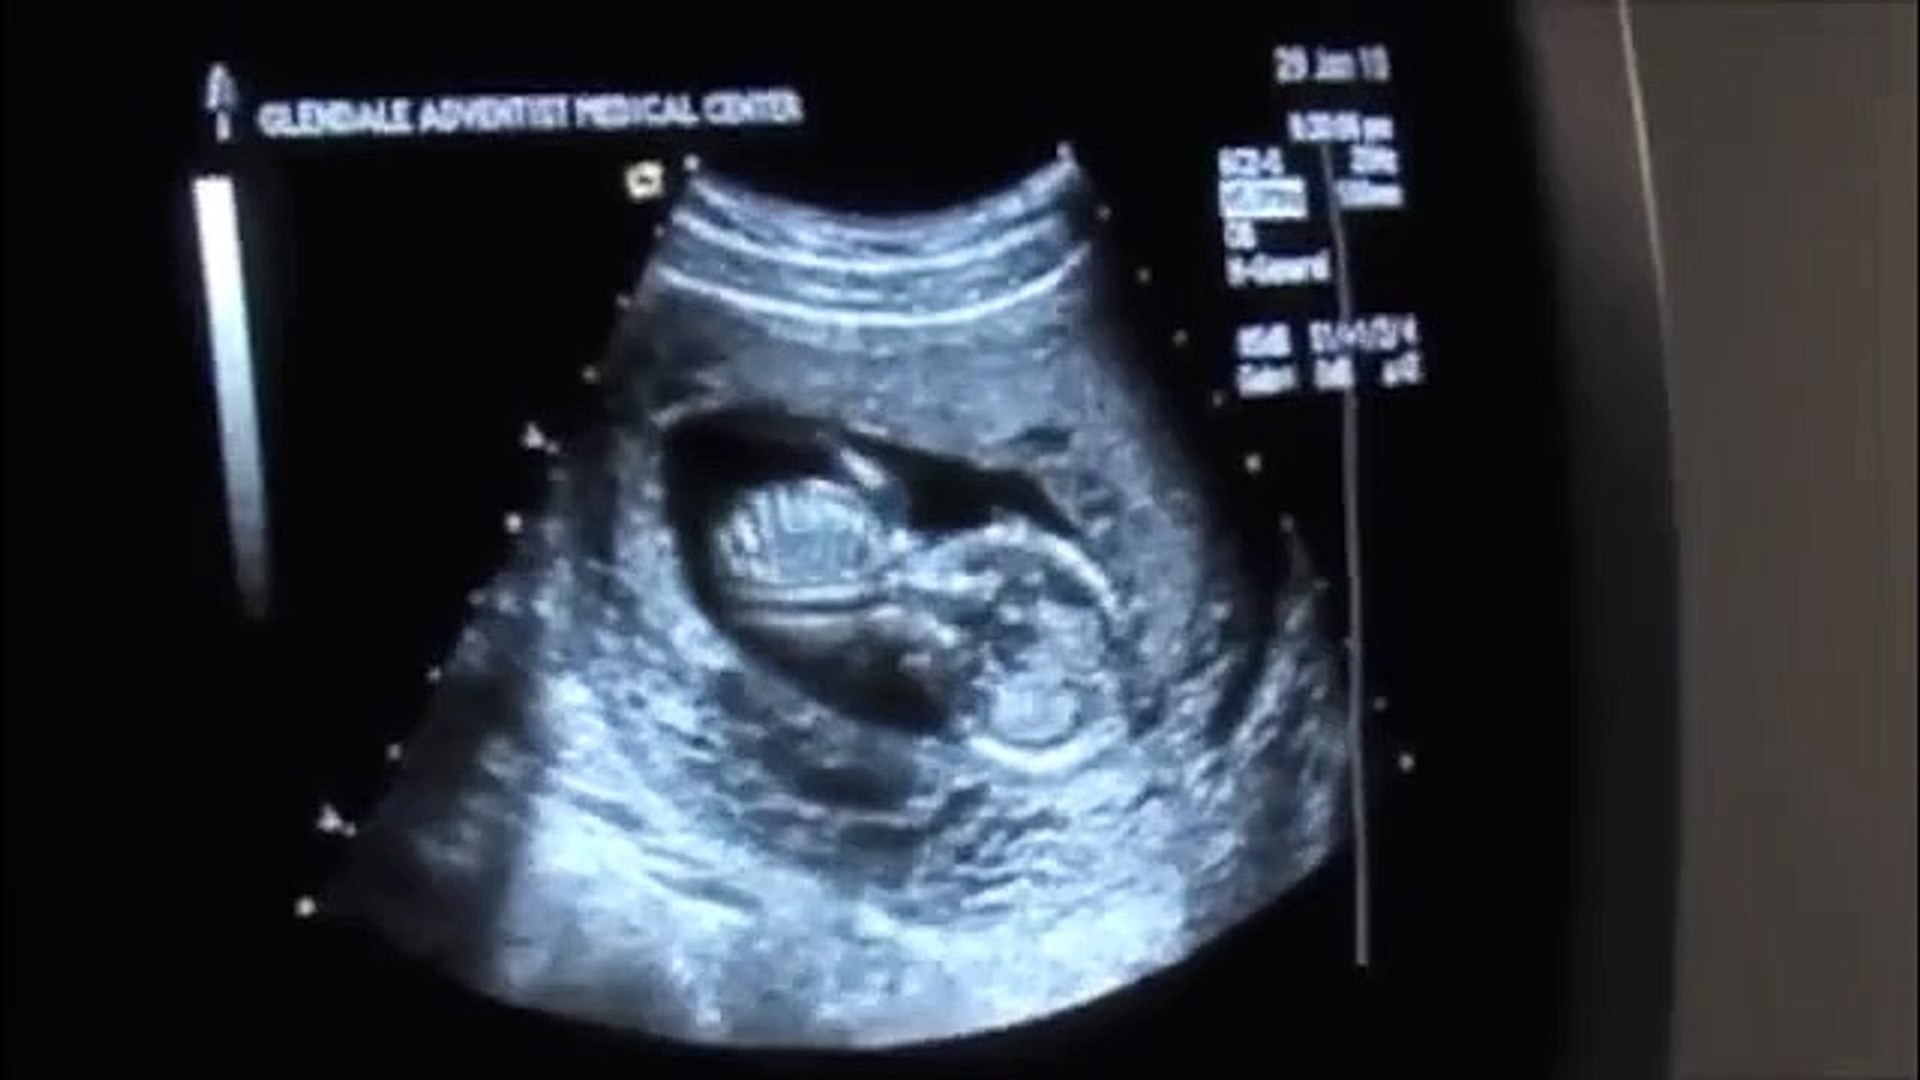

Boy 23 Week 3d Ultrasound

18 to 20 week ultrasound. Find out more about her mobility and other exciting pregnancy milestones at. I had my 23 week ultrasound today and it was fab. Ultrasound of 12 weeks unborn baby boy fetal jsnow in there hes fetus not embryo anymore.

What it would look like now that baby is at 23 weeks she may be walking around your belly a lot. All things 20 week ultrasound duration. What is the accuracy of the ultrasound. Boy ultrasound signs.